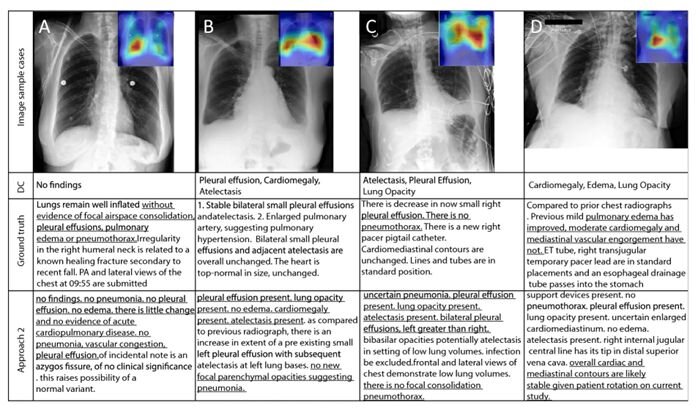

В первом ряду таблицы — рентгеновские снимки грудной клетки, во втором — диагноз врача коротко, в третьем — более развернутый комментарий врача, в четвертом — описание, сгенерированное нейросетью. Подчеркнутые фрагменты демонстрируют, что версии искусственного интеллекта и врача в целом сходятся, хоть сам текст и нуждается в редактуре / ©Александр Селиванов и другие / Scientific Reports